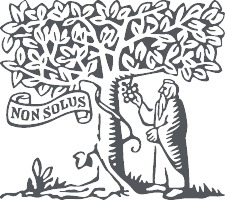

Figs. 63 y 64. Tras la anestesia, siempre debe comprobarse el ajuste correcto de la plantilla de perforación en el maxilar.

Fig. 68. La plantilla de perforación osteosoportada para el maxilar inferior, fijada in situ.